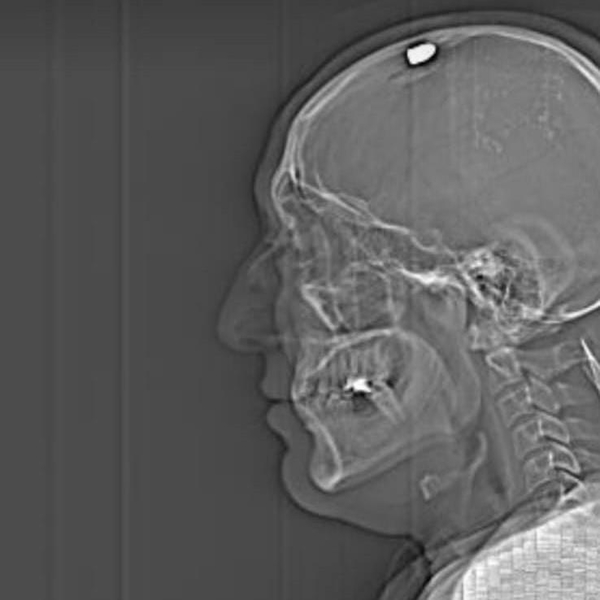

Savaş Koç, bugünkü duruşmada verdiği ifadesinde kendisini vuran Fırat Sucuğ ve yanındaki kuzenin de akrabaları olduğunu söyleyerek, “İşe giderken beni aradı ve Alper’i sordu, evine götürmemi istedi. Ben de bunu kabul etmedim. ‘Ben Alper’i vuracağım’ dedi. O sırada ben iş yerine gittim. Çay aldım, içeri girdim. O sırada iki kişi geliyor bunlar. Kapının önünde benim üzerime geldiler. O sırada Fırat, belinden silahı çıkardı ve bana doğrulttu. İki sefer tetiğe bastı; ama ateş almadı. Sonra Fırat silahını düzeltmişti. O sırada ben can havliyle kendimi korumaya çalışıyordum. En sonunda beni vurdu. Tekrar bir daha beni öldürmesin diye ben ölü numarası yaptım, hareketsiz durdum. Ama her şeyi duyuyordum. Yani ben adaletin şu an için yerini bulmasını istiyorum. Hak ettikleri cezayı almalarını istiyorum. Şans eseri yaşıyorum şu an. O kurşun bir santim daha içeri girse şu an ayakta olmayabilirdim” dedi.

Savaş Koç’un avukatı Ali Erdem Gündoğan ise “Müvekkilin başına hedef alarak ateş ediyor. Kurşun beyine çok fazla zarar vermeden beyin tasının orada kalıyor. Müvekkil yere düşerken her şeyin farkında ve diyor ki ‘Ben o anda olayların hepsini görüyordum; fakat tekrar bana ateş etmesinler’ düşüncesiyle hareketsiz kalıyor, ölü taklidi yapıyor. Daha sonra bu şahıslar yakalanıyor. Müvekkil bunların kendilerini öldürme kastıyla geldiklerini söylüyor. Aslında müvekkil başkasının yerine kendini feda etmiştir. Yani o şahsın adresini vermiş olsaydı, o şahsı vuracaklardı. Adresi vermediği için müvekkili vuruyorlar” diye konuştu.